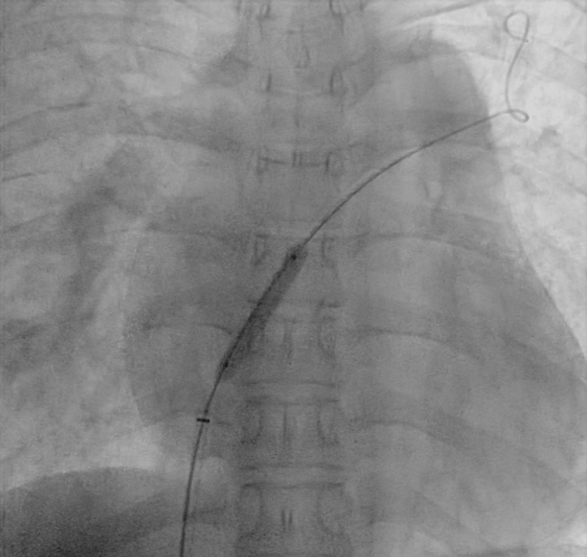

在局麻下为患者行右心导管检查,测量左房压16/8(11) mmHg ,右房压23/11(15) mmHg,肺动脉压167/93(116)mmHg,左右房压差为4 mmHg,全肺阻力 1605 dyn·s·cm-5, 肺血管阻力 1453 dyn·s·cm-5,心输出量 5.6 L/min,心指数 3.7 L/min/m2 ,不吸氧的情况下SPO2 92%,经胸超声定位后行房间隔穿刺,送入预塑形的左房导丝建立轨道,选择6mm外周动脉高压球囊对房间隔进行谨慎扩张三次,送入10F输送系统,体外排气充分后送入心房分流器(WKASD 20-6mm)至房间隔处支撑开此前球囊撕开的不规则房间隔造口,透视及超声观察分流器形态位置良好,释放封堵器。

术后测量左房压16/8(11) mmHg,右房压 17/8(12) mmHg,肺动脉压173/87(116)mmHg,左右房压差为1 mmHg。右房平均压较术前下降3 mmHg,全肺阻力 2167 dyn·s·cm-5,心输出量6.2 L/min,心指数 4.1 L/min/m² ,SPO2 90% ,心输出量较术前显著改善,氧饱和度稍下降。

术后心脏超声提示:房间隔过隔分流存在,孔径约5mm,分流速度 0.9 m/s。

心房分流器植入术